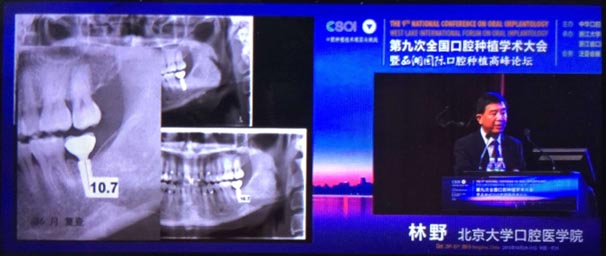

2015年10月29日第九次全國(guó)口腔種植學(xué)術(shù)大會(huì)暨“西湖國(guó)際”口腔種植高峰論壇在浙江省人民大會(huì)堂隆重開(kāi)幕。這是中華口腔種植專業(yè)委員會(huì)主辦的兩年一度的全國(guó)性學(xué)術(shù)會(huì)議,代表了中國(guó)口腔種植學(xué)發(fā)展的水平和方向。

會(huì)議期間國(guó)內(nèi)知名口腔專家針對(duì)當(dāng)前口腔種植領(lǐng)域熱點(diǎn)進(jìn)行了精彩的學(xué)術(shù)演講。其中北京大學(xué)口腔醫(yī)學(xué)院林野教授的演講主題是“種植體設(shè)計(jì)及臨床意義”。

威高演講中林野教授對(duì)國(guó)產(chǎn)品牌WEGO牙種植體系統(tǒng)的設(shè)計(jì)和臨床表現(xiàn)表示肯定,向在座觀眾展示了WEGO牙種植體系統(tǒng)的臨床病例。病例對(duì)76枚WEGO牙種植體進(jìn)行了平均21個(gè)月的追蹤觀察,結(jié)果表明WEGO牙種植體脫落、松動(dòng)、種植體周?chē)‖F(xiàn)象均為0,頸部骨吸收平均值為0.20mmSD值0.07。